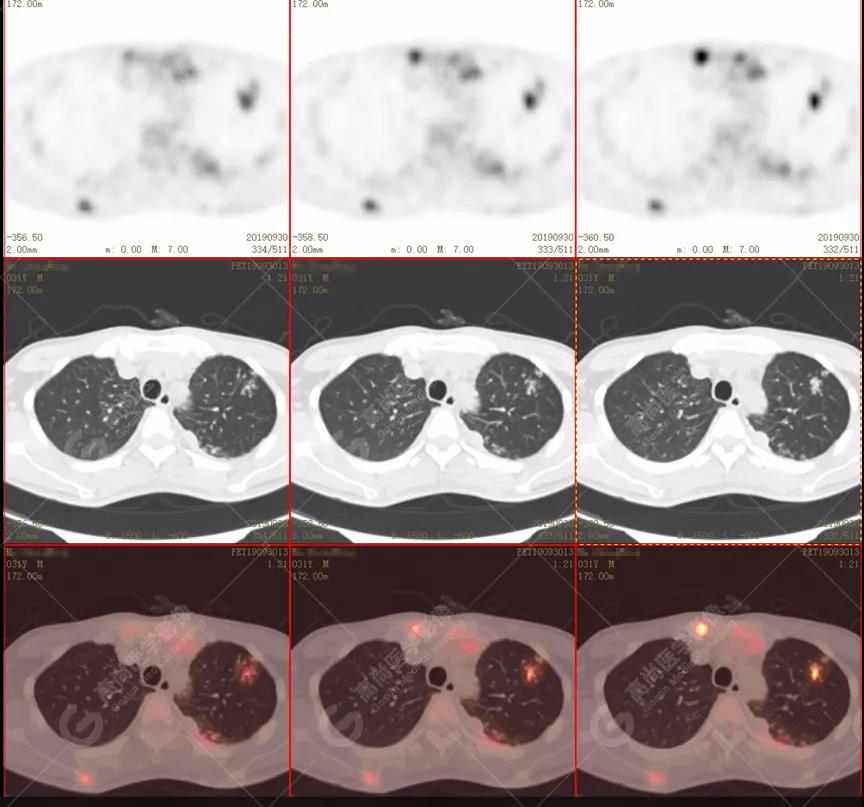

左肺上葉尖后段及下葉背段多發(fā)簇狀斑點(diǎn)狀高代謝灶

左側(cè)胸膜結(jié)節(jié)樣增厚,代謝不同程度增高

雙肺、左側(cè)胸膜多發(fā)結(jié)節(jié)影,全身多處骨質(zhì)破壞,全身多發(fā)淋巴結(jié)腫大,代謝攝取不均勻性增高。

2.全身多系統(tǒng)、多形態(tài)、多發(fā)病灶(肺部、胸膜、淋巴結(jié)、骨),18F-FDG攝取不均性增高;

特征:肺部病灶簇狀分布,上葉尖段及下葉背段為著;腫大淋巴結(jié)分布不對稱,無融合、中央有壞死改變,與淋巴瘤、轉(zhuǎn)移瘤等有一定的鑒別診斷意義;

1. 好發(fā)上葉尖后段及下葉背段(血氧飽和度豐富);